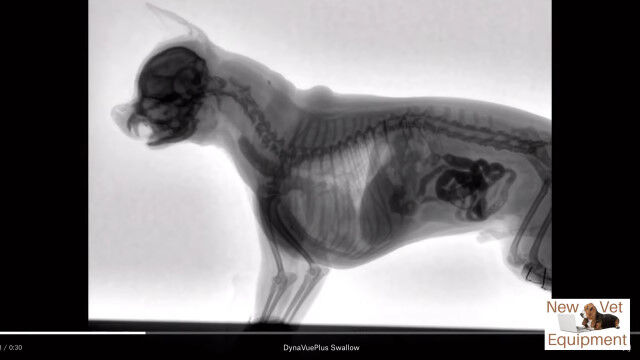

動物用レントゲンシステム、ダイナビューを用いて撮影された、犬がエサを食べる最中の体内の様子。

口から食道を通り、ゆっくり胃袋へ流れ込む様子が動画ではっきり確認できる。

Youtubeの概要欄に記載がなくて分からなかったけど、これ犬種はなんだろうね。

Veterinary Fluoroscopy - Watch the Swallow!